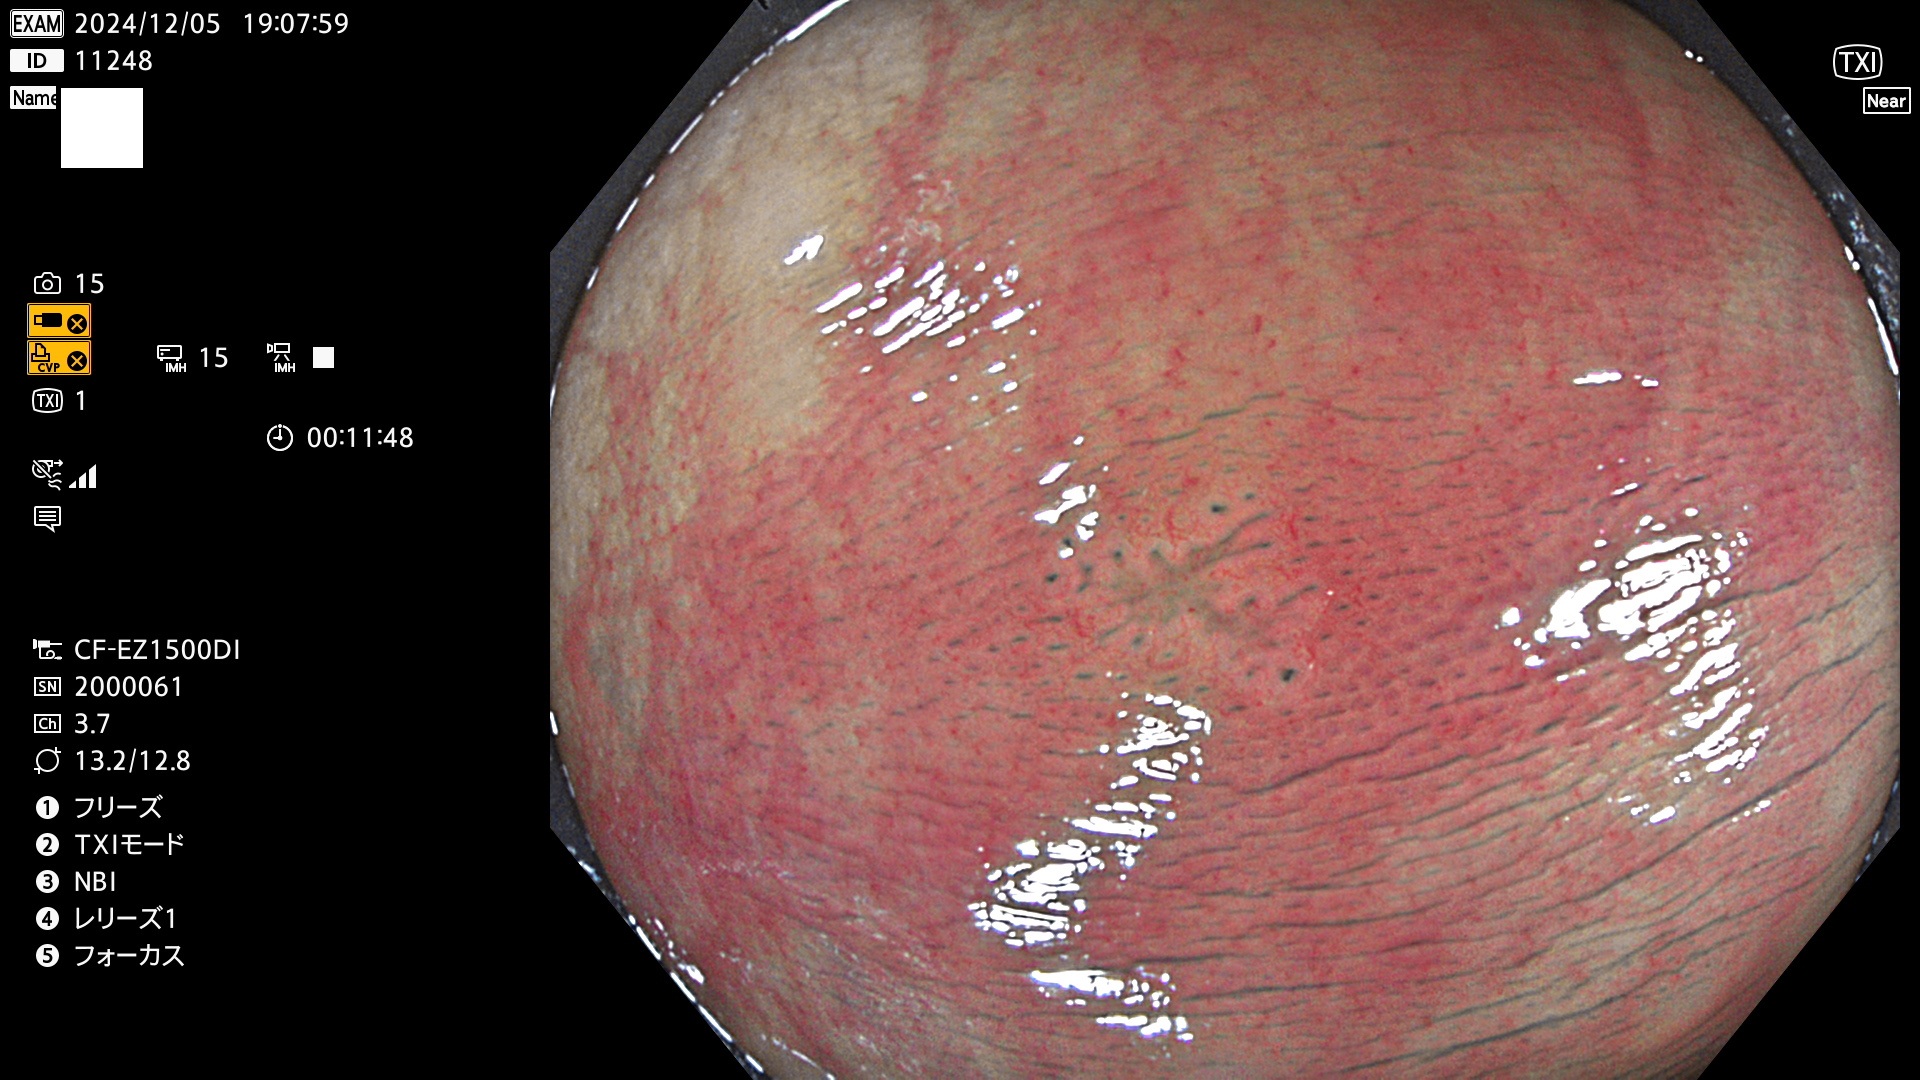

今週のUb、Uc型腺腫

完全に平坦な物をUb、陥凹している物をUcと呼びます。最も発見が難しく危険な病変です。

毎週の検査(木・金・土・日)に発見されたUb、Uc型・腺腫を、その週の日曜の夜にUPし1週間、提示します。

抽出の対象期間 2024年12月5日〜12月8日の4日間(48件の検査)4件 (4/48=8%)